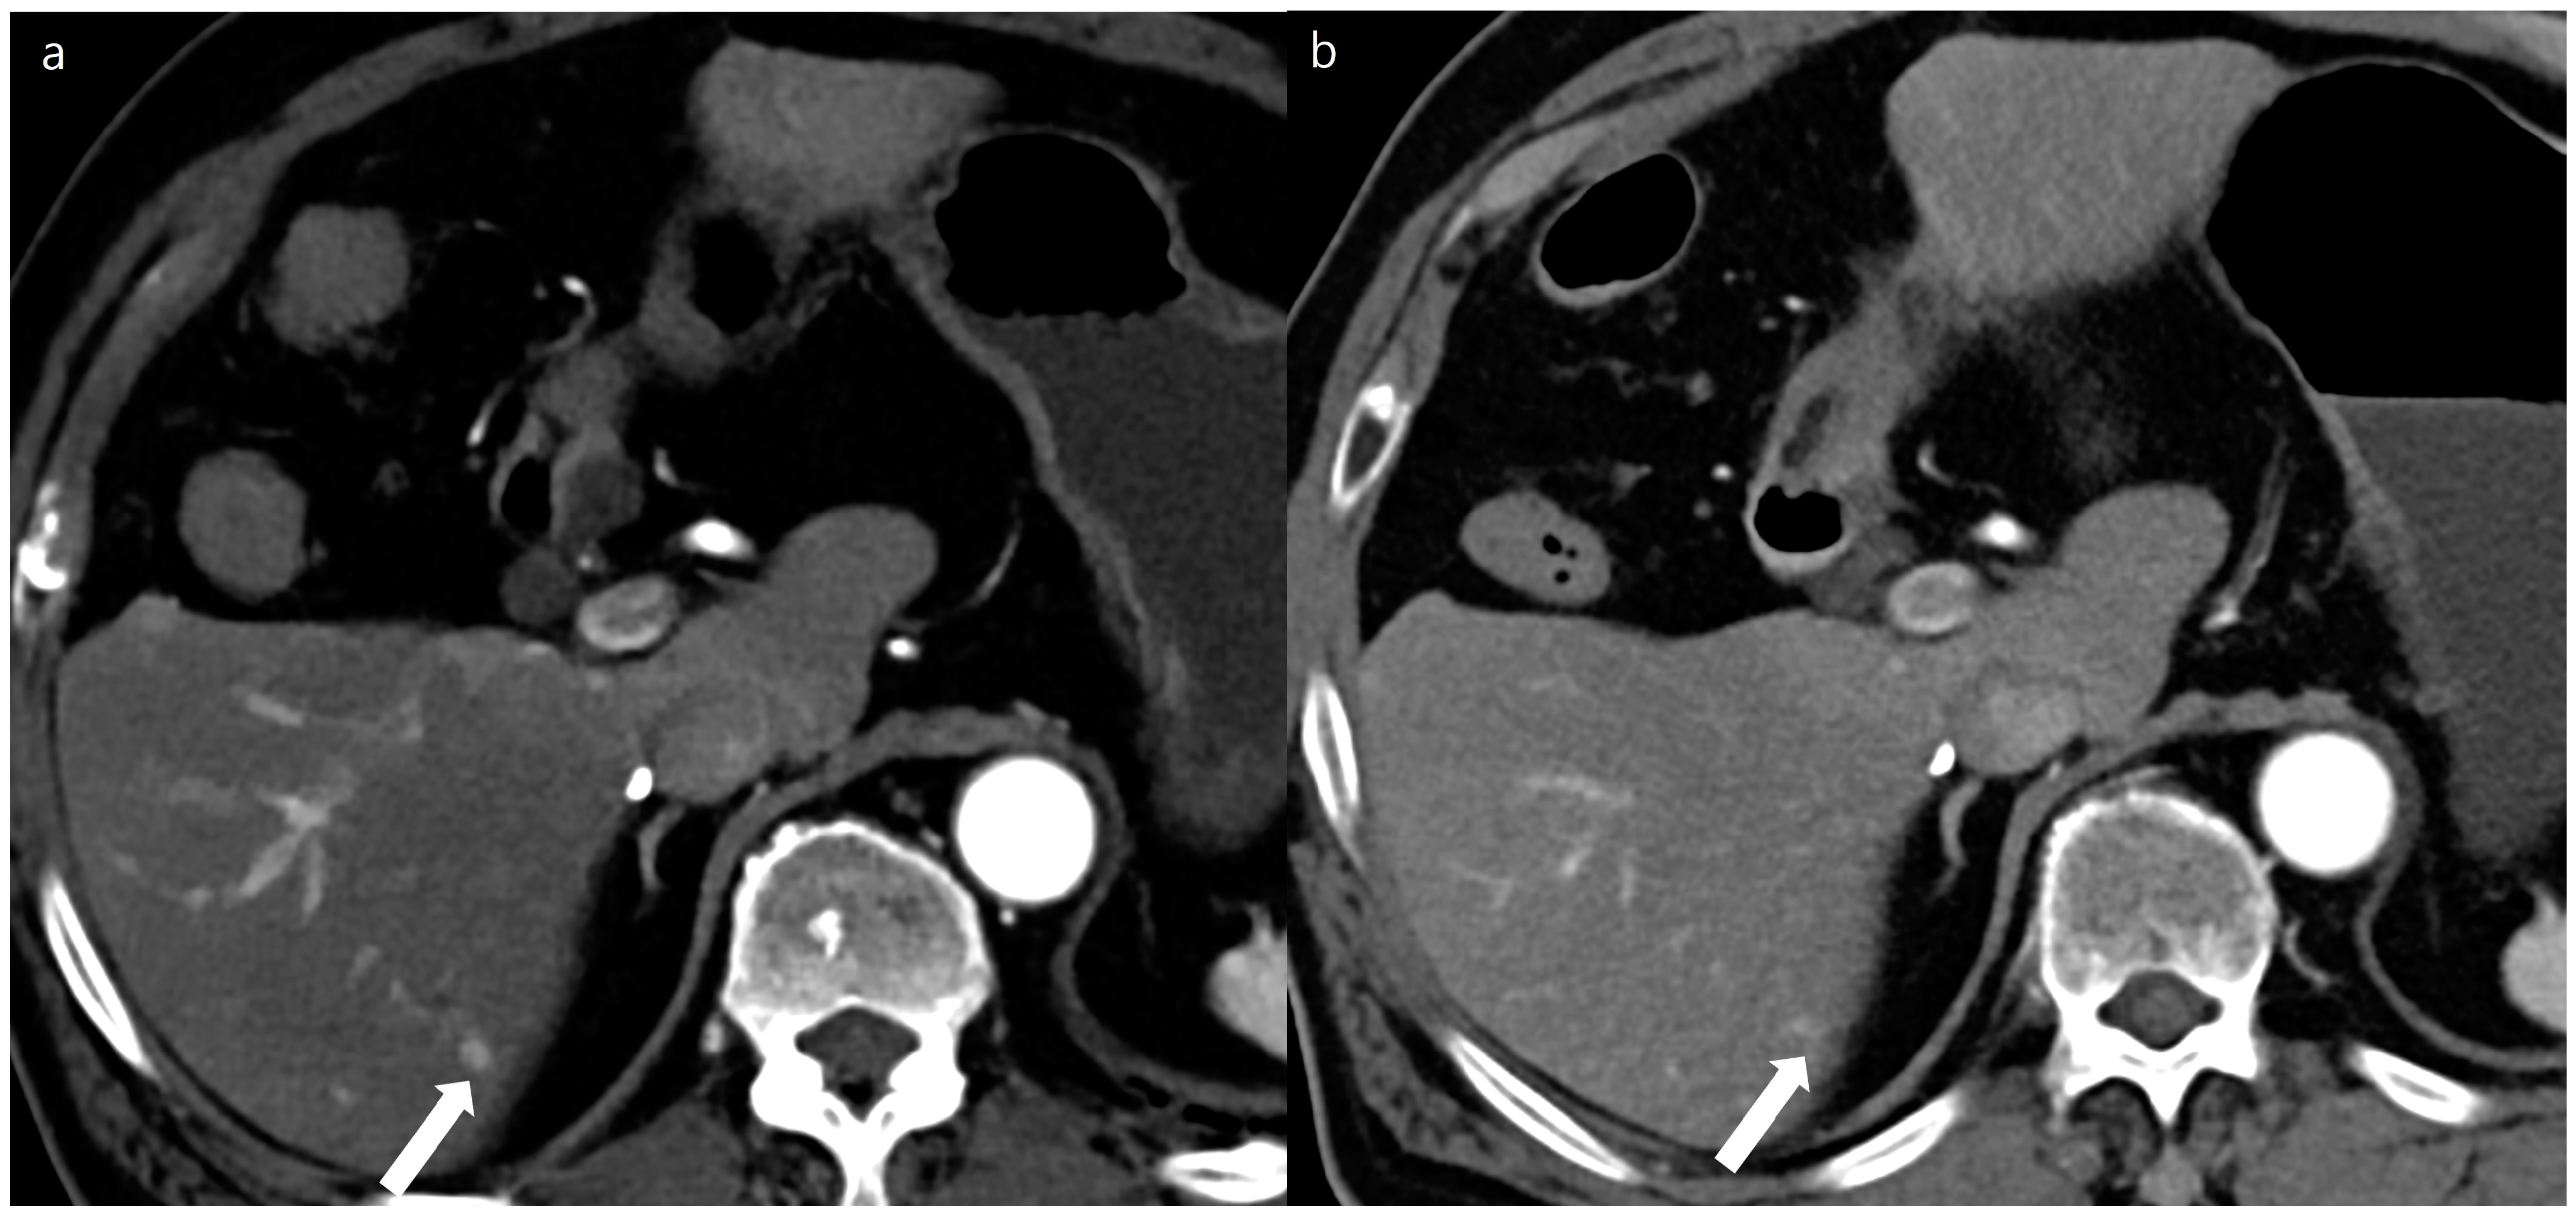

Figure 4. A 54-year-old man with a 0.4 cm sized small focal low density at segment 2 of the liver (arrows). A double low-dose CT using a deep-learning-based contrast-boosting model (a) shows better conspicuity (Reviewer 1, 4; Reviewer 2, 5) of the focal lesion (arrows) than standard-dose CT using hybrid iterative reconstruction (Reviewer 1, 2; Reviewer 2, 1) (b) at portal phase images (time interval: 11 months). Two reviewers evaluated the double low-dose CT using a deep-learning-based contrast-boosting model and standard-dose CT using hybrid iterative reconstruction. The results demonstrated no difference in overall image quality.

Figure 5. An 82-year-old man with a 0.5 cm sized enhancing nodule at segment 6 of the liver (arrows). A double low-dose CT using a deep-learning-based contrast-boosting model (a) shows better conspicuity (Reviewer 1, 5; Reviewer 2, 4) of the focal lesion (arrows) than standard-dose CT using hybrid iterative reconstruction (Reviewer 1, 5; Reviewer 2, 3) (b) at arterial phase images (time interval: 4 months). Two reviewers evaluated the double low-dose CT using deep-learning-based contrast-boosting model and standard-dose CT using hybrid iterative reconstruction. The results demonstrated no difference in overall image quality.